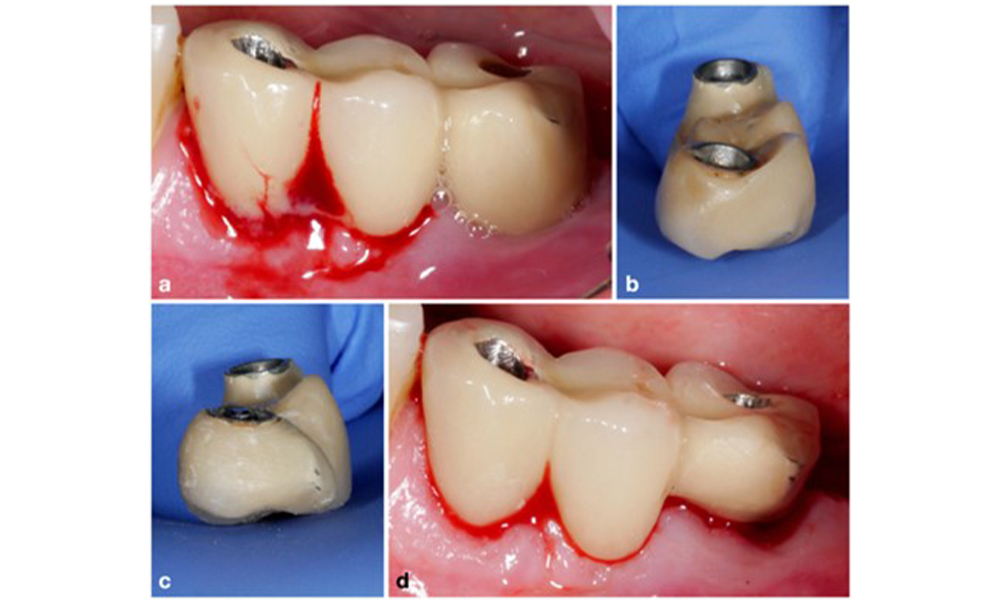

The World Workshop on the Classification of Periodontal and Peri‐Implant Diseases and Conditions from 2017 established diagnostic criteria for peri-implant mucositis and peri-implantitis (Renvert et al. 2018). Peri-implant mucositis is defined as (1) presence of inflammation around the implant (i.e., redness, swelling, line or drop of bleeding within 30 seconds of probing), combined with (2) no additional bone loss after initial healing (figure 1).

Peri-implantitis is identified by (1) signs of inflammation similar to mucositis, (2) radiographic evidence of bone loss after initial healing and (3) an increase in probing depth compared to measurements taken shortly after placing the prosthetic reconstruction (figure 2). In the absence of previous radiographs, radiographic bone level of ≥ 3 mm along with bleeding on probing and probing depths ≥ 6 mm, indicates peri‐implantitis.

The expected bone loss after initial healing attributed to marginal bone remodelling, varies based on factors such as the implant system or type. For instance, 1–2 mm bone loss is generally considered “normal” for bone level implants with an external connection (figure 2d, implant in position 23).